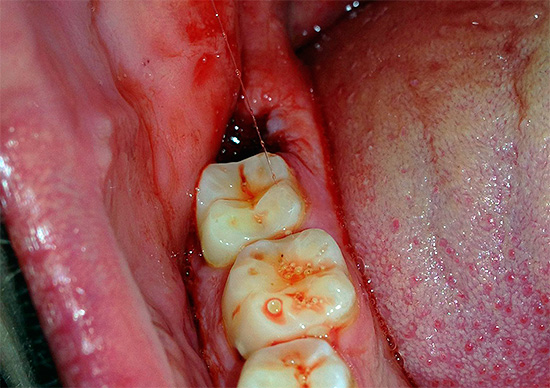

Devido à massa e densidade do osso da mandíbula, não é possível realizar uma aderência e balanço normais do dente (especialmente em caso de dificuldade em erupção, quando apenas 20 a 30% da coroa pode estar na superfície). Mesmo com uma coroa bem definida e sem cárie, o balanço do dente do siso inferior, localizado na espessura de um osso maciço, é muito, muito problemático, especialmente quando as raízes têm o número e a localização mais imprevisíveis na mandíbula.

Infelizmente, mesmo depois que o dente do siso inferior já foi removido, as consequências da cirurgia experiente ainda podem ser sentidas no futuro - no entanto, uma grande superfície da ferida com tecidos rasgados em torno dele muitas vezes permanece na cavidade oral. Os problemas típicos que você pode encontrar ao mesmo tempo são sangramentos graves do orifício, aumento gradual da dor, inchaço da bochecha e gengivas, inflamação e supuração das paredes do orifício (alveolite) e outros.